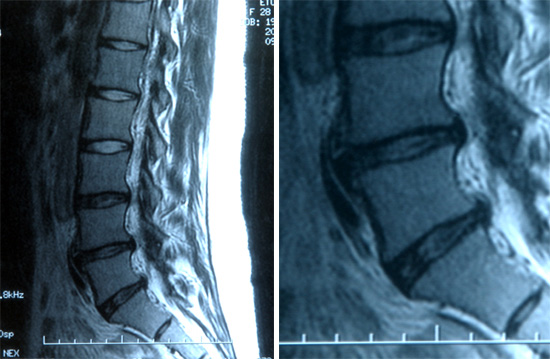

椎間板ヘルニアのMRI画像を掲載します。本症例は完全な髄核前方脱出とまでは言えませんが、

参照資料としてください。髄核の脱出を観察しやすいように脱出部位を拡大しました。